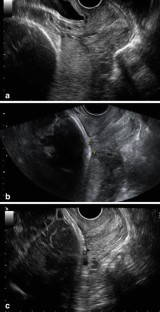

Fig. 1